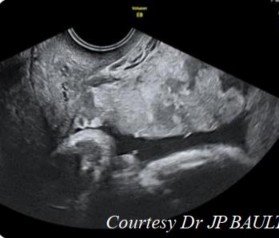

- Tiêu chuẩn 3: mất hình ảnh khoảng ranh giới giữa cơ tử cung và thành bàng quang, lớp cơ tử cung mỏng < 1 mm, thành bàng quang bị đẩy lồi vào trong lòng của nó (dấu hiệu giả khối u) [30].

Hình 1.3: Hình ảnh bất thường ở thành bàng quang [31]

Hình 1.4: Hình ảnh siêu âm doppler màu RCRL [30]

Theo các tiêu chuẩn mô tả trong Y văn thì tiêu chuẩn 1 và 2 gặp ở 100% số trường hợp, trong đó hình ảnh siêu âm 2D có các nang chứa dịch nằm trong nhu mô rau là dễ dàng nhận ra nhất và có giá trị cho chẩn đoán thậm chí từ rất sớm, các dấu hiệu khác thì khó nhận ra hơn trên siêu âm, đó là thành tử cung lồi vào trong lòng bàng quang (dấu hiệu giả khối u).